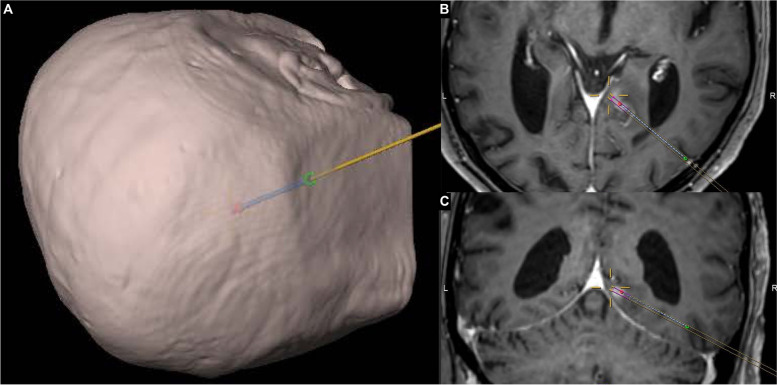

Fig. 1.

Stereotactic planning and cannula position verification in an exemplary patient. A three-dimensional image-based head reconstruction with planned biopsy trajectory from a right occipital approach. B axial and C coronal T1-weighted contrast-enhanced MRI sequences. The target is indicated by the crosshairs; mainly out of plane are the planned trajectory (parallel lines), the planned biopsy region (violet), as well as the intra-procedural CT-verified tip, intracranial trajectory and entry point of the biopsy cannula (red, dashed line and green point, respectively)

A total of 7 stereotactic trajectories in 7 patients have been verified intraoperatively using a mobile CT unit (Table 1). This study was approved by the local ethics committee (Kantonale Ethikkommission Zürich, BASEC-Nr.: 2020–00,810). For all patients, thin-cut (slice thickness of at most 1 mm) T1-weighted sequences with contrast were used for stereotactic trajectory planning with the software iPlan® (Brainlab, Feldkirchen, Germany). For ID 5 a PET-MR and for IDs 1, 2 and 6, additional FLAIR sequences were fused for preoperative planning. For the operation, patients were positioned depending on the planned trajectory and site of lesion, with their head fixated in a DORO® radiolucent headrest (ProMed Instruments, Freiburg, Germany). An intraoperative, pre-procedural CT examination was obtained using the Airo® mobile CT (Brainlab, Feldkirchen, Germany) with fixed collimator and reconstruction slice width (1.06 mm and 1.0 mm, respectively) and a kVp of 120. mAs was 325 for IDs 1, 4, 7 and 260 for all others. The scan was automatically stereo-localized by the Brainlab Curve neuronavigation system (Brainlab, Feldkirchen, Germany) and computationally fused with the pre-operative MRI images. Stereotactic Nashold-type disposable brain cannula (Brainlab, Feldkirchen, Germany) biopsy was performed using the VarioGuide® (Brainlab, Feldkirchen, Germany) frameless stereotactic guidance tool. Specimen were extracted for frozen sections and final histological analysis with routine and immunohistochemical studies as indicated. While waiting for the results of the frozen sections, an intra-procedural CT was obtained using the Airo® unit to verify the correct position of the in-situ biopsy cannula (Fig. 1). Finally, the cannula was removed and surgery finished.